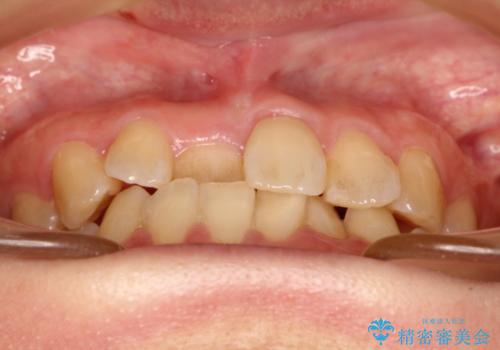

- 前歯の歯並びが気になるとのことで来院されました。

右上の1番目の歯が内側に入り込んでしまっており、その歯がの先端がすり減ってしまっていました。

インビザラインによる矯正治療で前歯の歯並びを改善し、セラミッククラウン装着により歯の形態の回復をする計画としました。